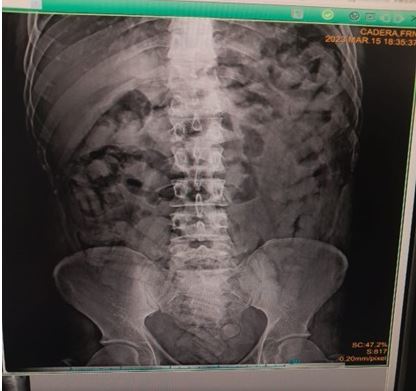

Y en el Centro Profesional de Salud Mendivelso, ubicado en la población de Coloncito, (Táchira), culminó el proceso de expulsión de 101 dediles de cocaína (1 kilo 195 gramos) que llevaba en su estómago Nelson Adolfo Rosales Ruiz.

Esta persona fue detenida el pasado miércoles cuando se desplazaba en una unidad de transporte público proveniente de Colombia y la cual fue revisada en la alcabala de El Pulpito (Táchira).